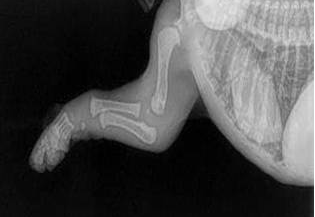

L'OSSATURE DU CHIOT

Leurs os ne se touchent même pas encore. Ils marchent si gentiment avec de grosses pattes souples et un mouvement bancal parce que leurs articulations sont entièr...